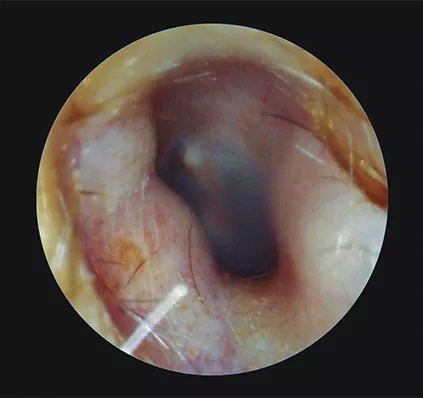

Las exostosis son neoformaciones de hueso en la porción medial del CAE. Son múltiples y bilaterales y surgen como resultado de una estimulación del periostio inducida por agua fría. (Fig. 5). Los osteomas, en contra, constituyen una sola formación. Suelen ser pedunculados y, a menudo, con núcleo vascular.

Aunque tanto la exostosis como los osteomas suelen ser asintomáticas y de crecimiento lento, a veces se recomienda la extracción de los mismos, pues una lesión agrandada puede llegar a ocluir el CAE provocando así una pérdida de audición conductiva y la posibilidad de infecciones.

Figura 5

Exostosis del conducto auditivo en un oído izquierdo. Se aprecian múltiples prominencias que disminuyen el calibre normal del conducto.